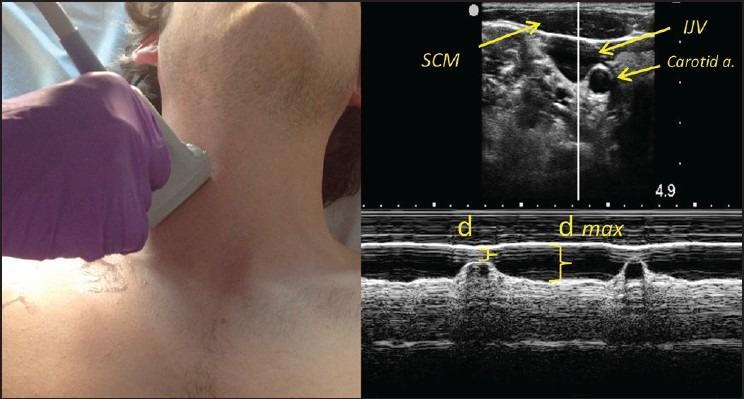

A prospective, observational study comparing IVC-CI and Fem- and/or IJV-CI was performed in two intensive care units (ICU) between January 2012 and April 2014. Concurrent M-mode measurements of IVC-CI and FV- and/or IJV-CI were collected during each sonographic session. Measurements of IVC were obtained using standard technique. IJV-CI and FV-CI were measured using high-frequency, linear array ultrasound probe placed in the corresponding anatomic areas. Paired data were analyzed using coefficient of correlation/determination and Bland-Altman determination of measurement bias.

2012 年 1 月至 2014 年 4 月,在两个重症监护病房(ICU)进行了一项前瞻性、观察性研究,比较了 IVC-CI 和 Fem-和/或 IJV-CI。在每次超声检查期间,同时采集 IVC-CI 和 FV-和/或 IJV-CI 的 M 模式测量值。使用标准技术获得 IVC 测量值。使用高频线性阵列超声探头在相应的解剖区域测量 IJV-CI 和 FV-CI。使用相关系数/确定系数和 Bland-Altman 确定测量偏差对配对数据进行分析。